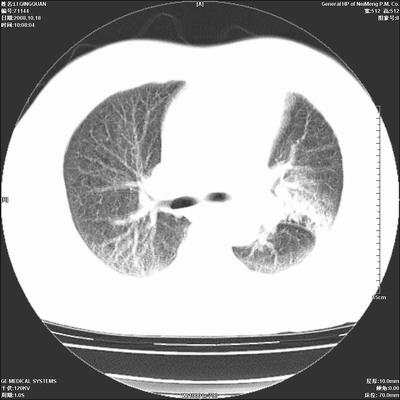

以下是引用ybing在2008-10-19 12:58:00的发言:[br]左肺上叶阻塞性炎症-建议支气管镜进一步检查除外中央型肺癌

以下是引用duguo在2008-10-19 13:59:00的发言:[br]左肺上叶支气管狭窄,首先考虑中心型肺癌伴阻塞性肺炎\\肺不张.

以下是引用随光逐影在2008-10-19 14:31:00的发言:[br]考虑左肺中央型肺癌并左肺上叶阻塞性肺炎,肺不张。